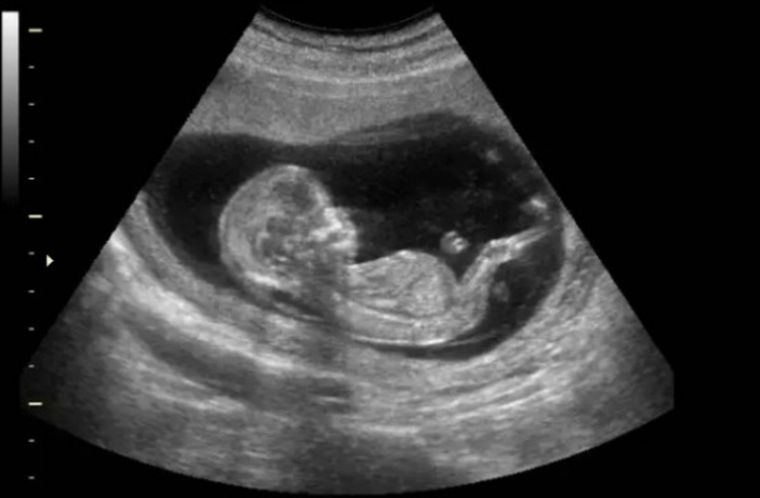

La presentación del proyecto de ley de Detección del Latido Cardíaco Fetal fue encabezada por el diputado de Unir, Alberto Asseff, quien contó que esto surgió a partir de conversaciones con especialistas (algunos científicos) y distintas organizaciones provida. “Científicamente, está probado que cuando hay un corazón que late, hay irrefutablemente vida. La detección es posible gracias a los equipamientos médicos existentes y se puede dar en la séptima u octava semana de gestación”, explicó Asseff a MDZ.

El proyecto de ley de Detección del Latido Cardíaco Fetal establece: "Los médicos, personal de salud y/o sistemas de salud no podrán realizar o inducir intencionalmente un aborto o interrupción del embarazo, si se detecta un latido cardíaco del/de los feto/s o niño/s en gestación, entendido el mismo como actividad cardíaca o contracción rítmica constante y repetitiva del corazón fetal, dentro del saco gestacional".

En caso de que no haya detección de latidos cardíacos, se deberá “repetir el estudio de ultrasonido a los efectos de confirmar el resultado negativo, con un intervalo mínimo de 72 horas entre el primer y el segundo ultrasonido”. Si en ninguno de los dos ultrasonidos se detectan latidos cardíacos fetales, el aborto se podría llevar a cabo.